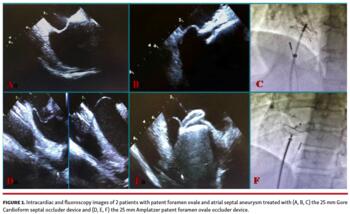

The present study, for the first time, directly compares the 2 most used and validated closure devices in patients with both a PFO and an ASA; ie, the APO device, which is more rigid, but extremely safe and effective, as shown by long-term follow-up studies, and the GSO device, which is softer than other devices, with a lower profile and without any bulky protrusion into the atria (Figure 1). These 2 devices were tested in a population with a high risk of recurrent embolic events or rRLS because all patients had a PFO with associated ASA and the vast majority of them had an adjunctive clinical and/or anatomical feature of risk. Nevertheless, we found that the clinical and echocardiographic results of the GSO favorably compare with those of the APO devices. No death or recurrent embolic events were registered at 1-year follow-up. In all patients, the 6-month and 1-year complete occlusion rate was 93% and 96%, respectively. The echocardiographic findings suggested that the occlusion process is not instantaneous, but rather occurs progressively in the months following the procedure. Postprocedural moderate/severe RLS had an occurrence rate of 13% in all patients (14% GSO vs 12% APO), 4% at 6-month follow-up in both groups combined, and 1% at 1-year follow-up (Figure 2). These results suggest that the definite occlusion time is not related to the different characteristics of the 2 devices, but seems to be related to their ability to firmly oppose the septum primum more closely due to the presence of a double-umbrella design. In addition, intraprocedural results were also similar in the 2 groups. The GSO and APO devices were successfully deployed in all patients, and fluoroscopy and procedural times were similar in both groups. Only 2 patients in the GSO group required device repositioning, and were subsequently repositioned and released using the same device. No device embolization was recorded in this series of patients. Thus, based on our experience, it is mandatory to select the appropriate device by utilizing an accurate morphological evaluation with TEE or ICE of the interatrial septum anatomy to minimize device-related complications and to achieve the optimal occlusion in order to reduce as much as possible the rRLS and, consequently, to make the interventions safer and more effective.